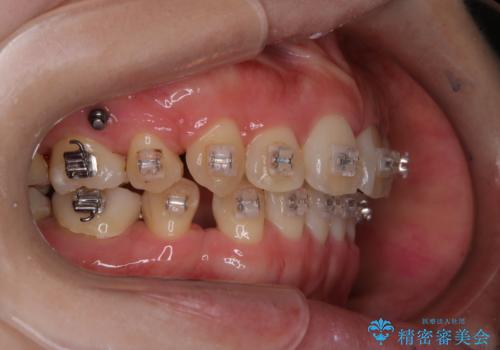

ハーフリンガルでのワイヤー矯正中にクリーニングで綺麗に

担当医 歯科衛生士